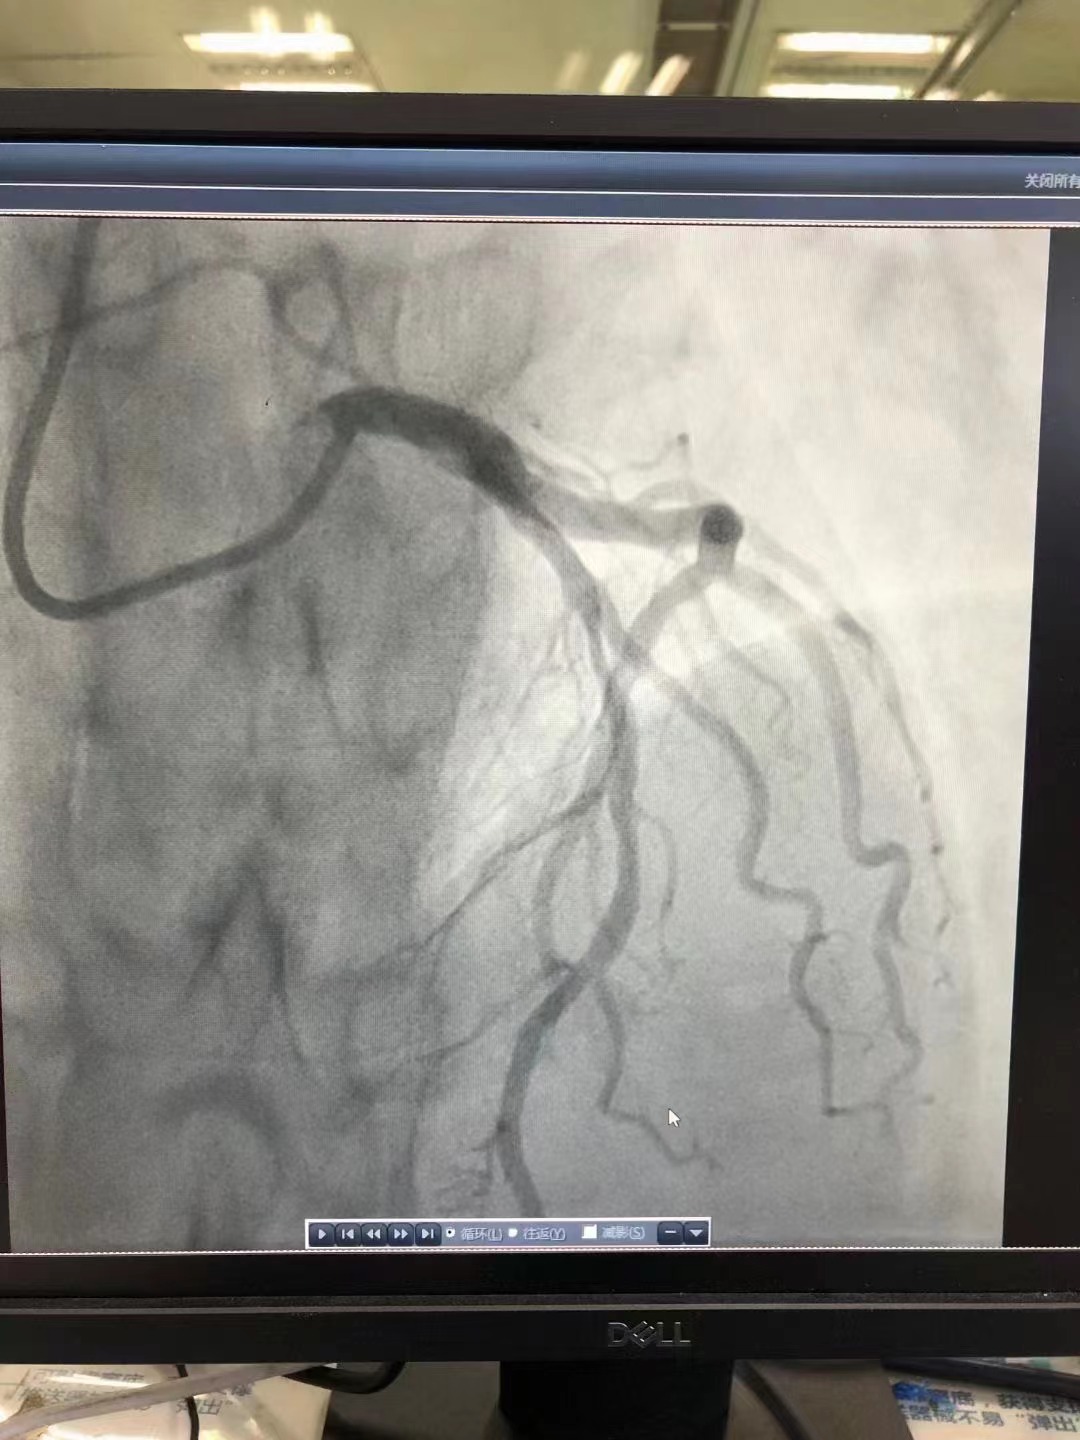

祝賀昆明醫科大學第一附屬醫院心內科王啟賢主任團隊成功為一位年輕患者植入一枚Xinsorb生物可吸收支架!

祝賀 昆明醫科大學第一附屬醫院心內科王啟賢主任團隊成功為一位年輕患者植入一枚Xinsorb生物可吸收支架!